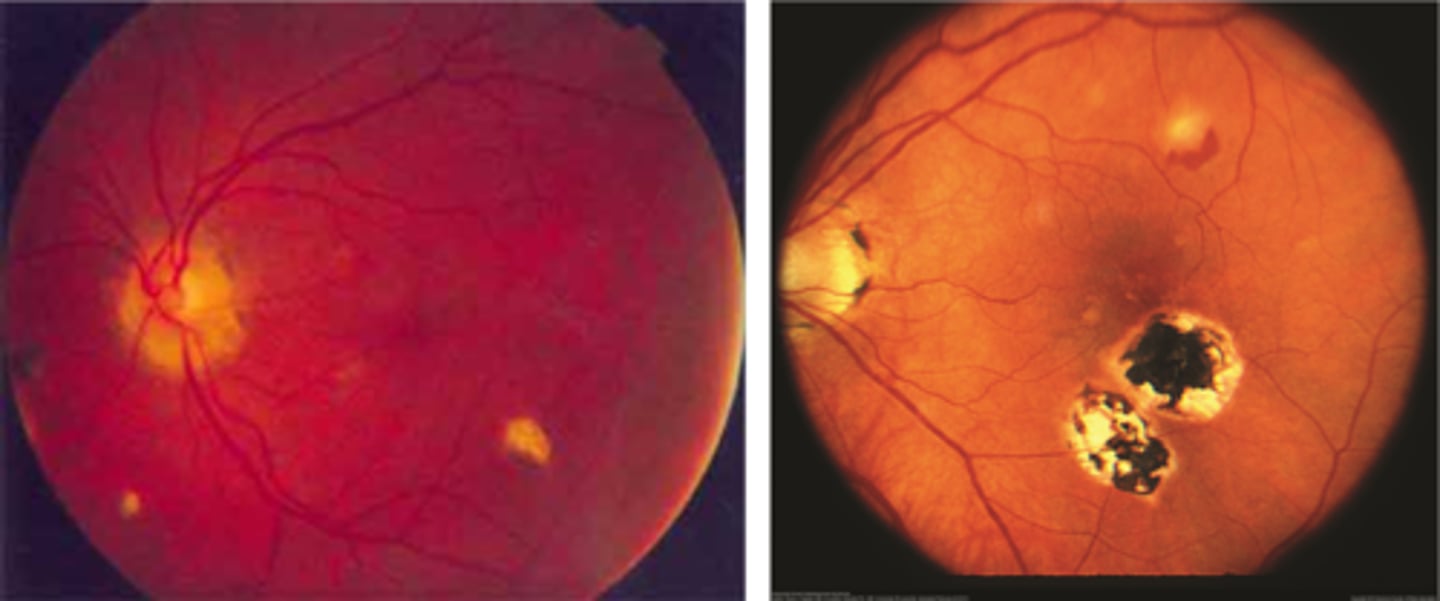

What findings of degenerative myopia are seen here?

PPA

crescent

lacquer cracks

What are lacquer cracks and what causes them?

breaks in Bruch's membrane that can expand and contract, mostly seen in degenerative myopia

How do lacquer cracks appear on fundoscopy?

jagged, irregular yellow lines showing sclera in the posterior pole

What is the main complication of lacquer cracks?

CNV in 29% of pt's